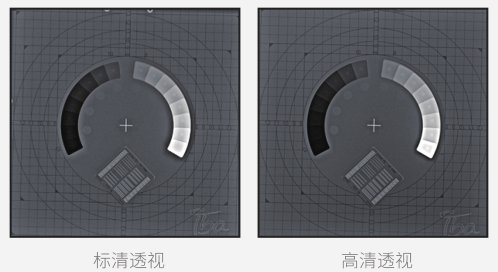

● 標清透視

以較少的輻射劑量呈現醫生所需的診斷圖像,為臨床初篩提供優質影像。

● 高清透視

在初診篩查的基礎上,使用高清透視功能輔助醫生再次確認病灶點,降低漏診、誤診的概率。

● 高清點片

在透視檢查下,可進行毫秒級高清點片,準確捕捉病灶,為醫生提供高清的診斷依據。